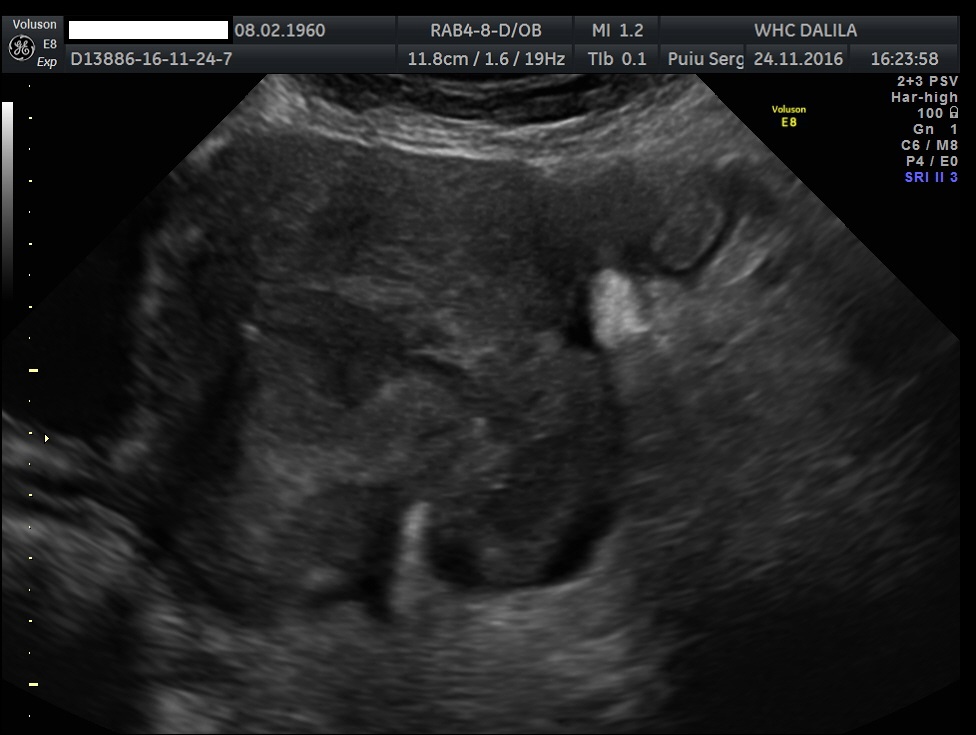

Transvaginal and transabdominal ultrasound scans were performed, which has shown the enlarged uterus with indistinct borders on the left side and a complex mass in left lower abdominal quadrant. A large irregular thick-walled, ill-defined multiloculated cystic/solid lesion with complex fluid collections and peripheral flow on color Doppler were seen. The anatomic distinction between the ovary and the fallopian tube could no longer be identified (Fig. 1). A tubo-ovarian abscess (TOA) was presumed. Endovaginal sonogram showed a dilated uterine cavity and cervical canal, filled with heterogeneous, complex fluid and echogenic masses (Fig. 2a-c). An intrauterine contraceptive was detected. A cavity within myometrium with low-level internal echoes fluid also was revealed (Fig. 2c). This complex adnexal mass was adherent to uterus and a communication between TOA and the cavity within myometrium with fluid-debris level fluid was detected (Fig. 3a-b). This finding presumed a perforation of the TOA into uterus, due to myometrium necrosis, and spontaneous drainages into uterine cavity through myometrium. Increased echogenicity of the pelvic fat and a small amount of free fluid in cul-de sac also were seen. Fluid movements through fistula canal between TOA and uterine cavity were clearly seen when a gently pressure by ultrasound probe was applied (Video 1).

Figure 1. Transabdominal scan. Enlarged uterus with indistinct borders on the affected side and a complex masses in left lower abdominal quadrant. Note a large thick-walled, ill-defined multiloculated cystic/solid lesion with complex fluid collections. The anatomic distinction between the ovary and the fallopian tube can no longer be identified.